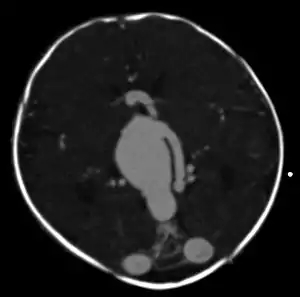

![]() | |

| Large arteriovenous malformation of the parietal lobe | |

An AVM diagnosis is established by neuroimaging studies after a complete neurological and physical examination.[4][9] Three main techniques are used to visualize the brain and search for AVM: computed tomography (CT), magnetic resonance imaging (MRI), and cerebral angiography.[9] A CT scan of the head is usually performed first when the subject is symptomatic. It can suggest the approximate site of the bleed.[2] MRI is more sensitive than CT in the diagnosis of AVMs and provides better information about the exact location of the malformation.[9] More detailed pictures of the tangle of blood vessels that compose an AVM can be obtained by using radioactive agents injected into the blood stream. If a CT is used in conjunctiangiogram, this is called a computerized tomography angiogram; while, if MRI is used it is called magnetic resonance angiogram.[2][9] The best images of an AVM are obtained through cerebral angiography. This procedure involves using a catheter, threaded through an artery up to the head, to deliver a contrast agent into the AVM. As the contrast agent flows through the AVM structure, a sequence of X-ray images are obtained.[9]